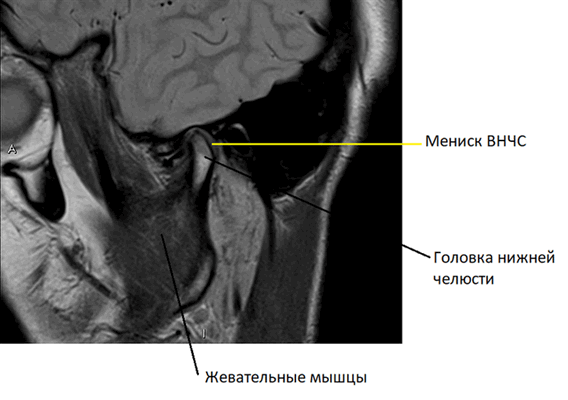

Анатомия височно-нижнечелюстного сустава

Височно-нижнечелюстной сустав (ВНЧС) — комбинированный парный сустав, образованный головками нижней челюсти и суставными бугорками (ямками), расположенными на височной кости. В полости ВНЧС имеются мениски — хрящевые пластинки, выполняющие роль прокладок и амортизаторов, а также обеспечивающие функцию сочленения. Благодаря этому височно-нижнечелюстной сустав способен выдерживать значительные нагрузки, возникающие при пережевывании пищи. По этой же причине ВНЧС имеет мощный связочный аппарат, укрепляющий и стабилизирующий сочленение.

На серии таких снимков, сделанных послойно в виде тонких срезов в нескольких плоскостях, легко распознать суставные хрящи, покрывающие головки нижней челюсти и суставной бугорок, образующие височно-нижнечелюстной сустав, мениск ВНЧС. Видны отдельные связки и сухожилия, жевательные мышцы. Любое возможное патологическое изменение, такое как воспаление сустава или новообразование, тут же будет видно на МРТ.